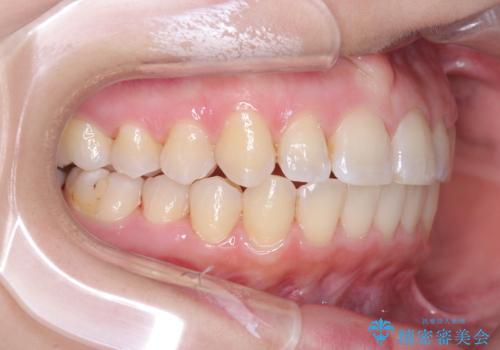

右下第二小臼歯の舌側転移の改善

- 患者様は、右下第二小臼歯が舌側に転移していることが主訴でした。診断の結果、抜歯を伴う矯正治療も検討しましたが、奥歯の遠心移動とIPR(インタープロキシマルリダクション)を行うことで、非抜歯で矯正を進めることが可能であると判断しました。治療計画では、審美ワイヤーを用いた2年間の治療で、歯列を整えつつ、臼歯関係や正中のバランスを維持しながら進めました。

非抜歯矯正では、歯の動きを慎重に調整することが求められます。本症例では、奥歯を遠心に移動させることで、舌側に転移した右下第二小臼歯の位置を改善しました。また、IPRを行うことで歯間スペースを確保し、無理なく歯列の調整を行いました。非抜歯での治療は、特に臼歯関係や正中を保ちながら治療できるというメリットがあり、最終的にはバランスの取れた歯並びを実現できました。審美ワイヤーを使用したことで、治療中も目立ちにくく、患者様の見た目にも配慮した治療を行いました。